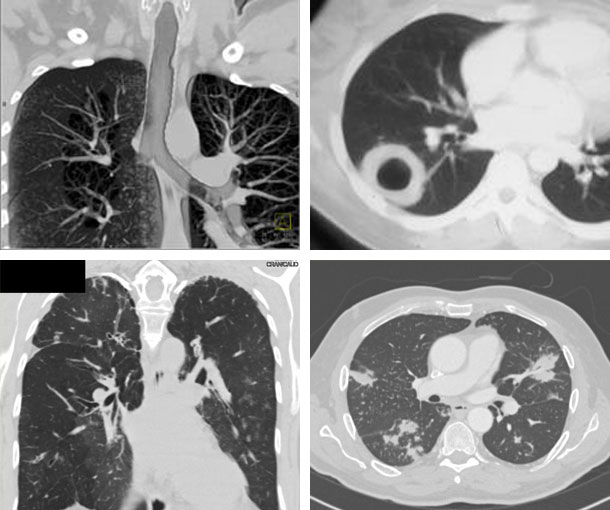

Chest CT Appearances

Granulomatosis With Polyangiitis CT Findings

- Cavitary nodules

- Large airway stenosis

- Nodules 1-10 cm in size

- Consolidation with or w/o hemorrhage

- Subglottic stenosis

- Adenopathy uncommon